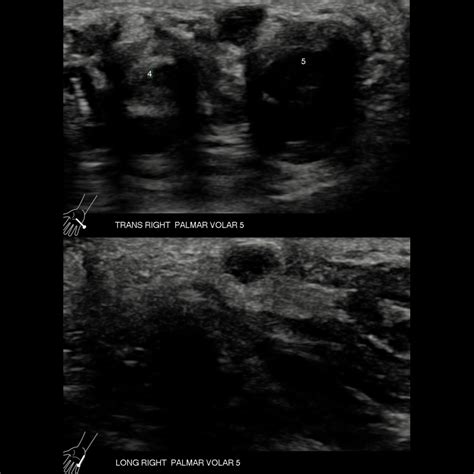

Close up of a hand showing a lump

A ganglion cyst palm of hand occurs when the clear, lubricating fluid found in joints—known as synovial fluid—leaks out and accumulates in a localized area. These cysts typically emerge from the sheath surrounding a tendon or directly from a joint capsule. Unlike cysts found on the back of the wrist, volar (palm-side) cysts are often smaller and firmer because they are trapped under tougher tissue layers.